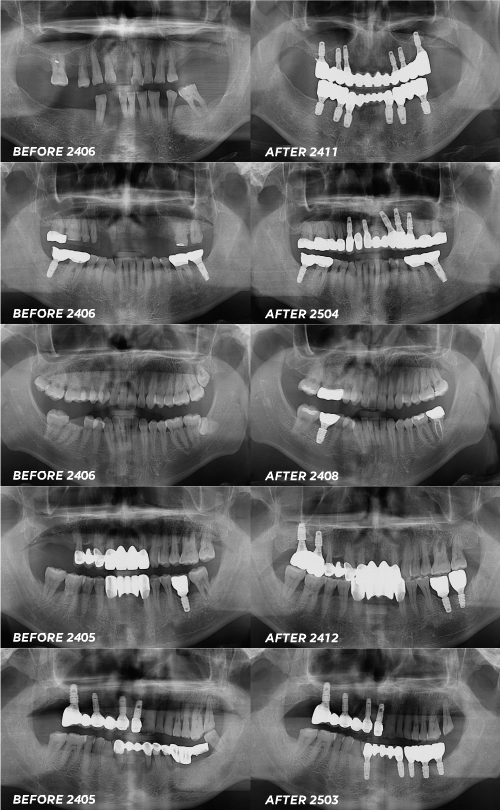

서울센텀치과 신사역 임플란트 사례